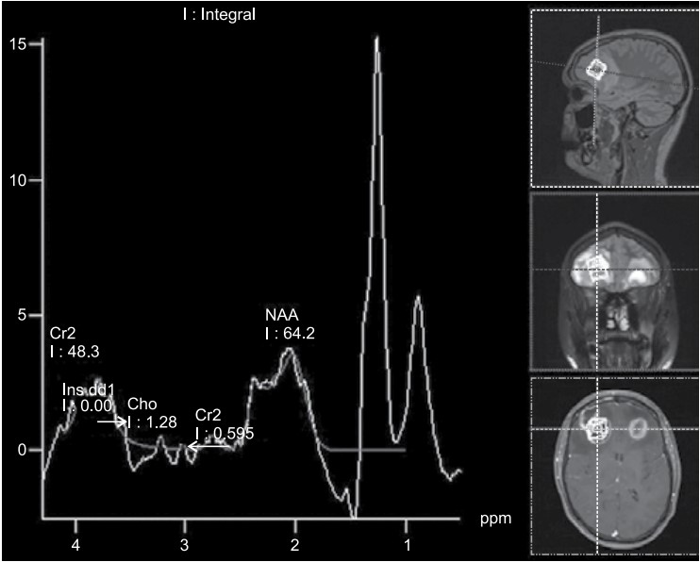

Paciente do sexo masculino, de 23 anos de idade, vem ao pronto-socorro com queixa de cefaleia e leve confusão mental com início há 7 dias.

O paciente realizou espectroscopia de prótons apresentada a seguir:

(Arquivo pessoal; imagem usada com autorização)

Assinale a alternativa correta em relação aos achados dessa sequência de espectroscopia de prótons e o caso clínico exposto.